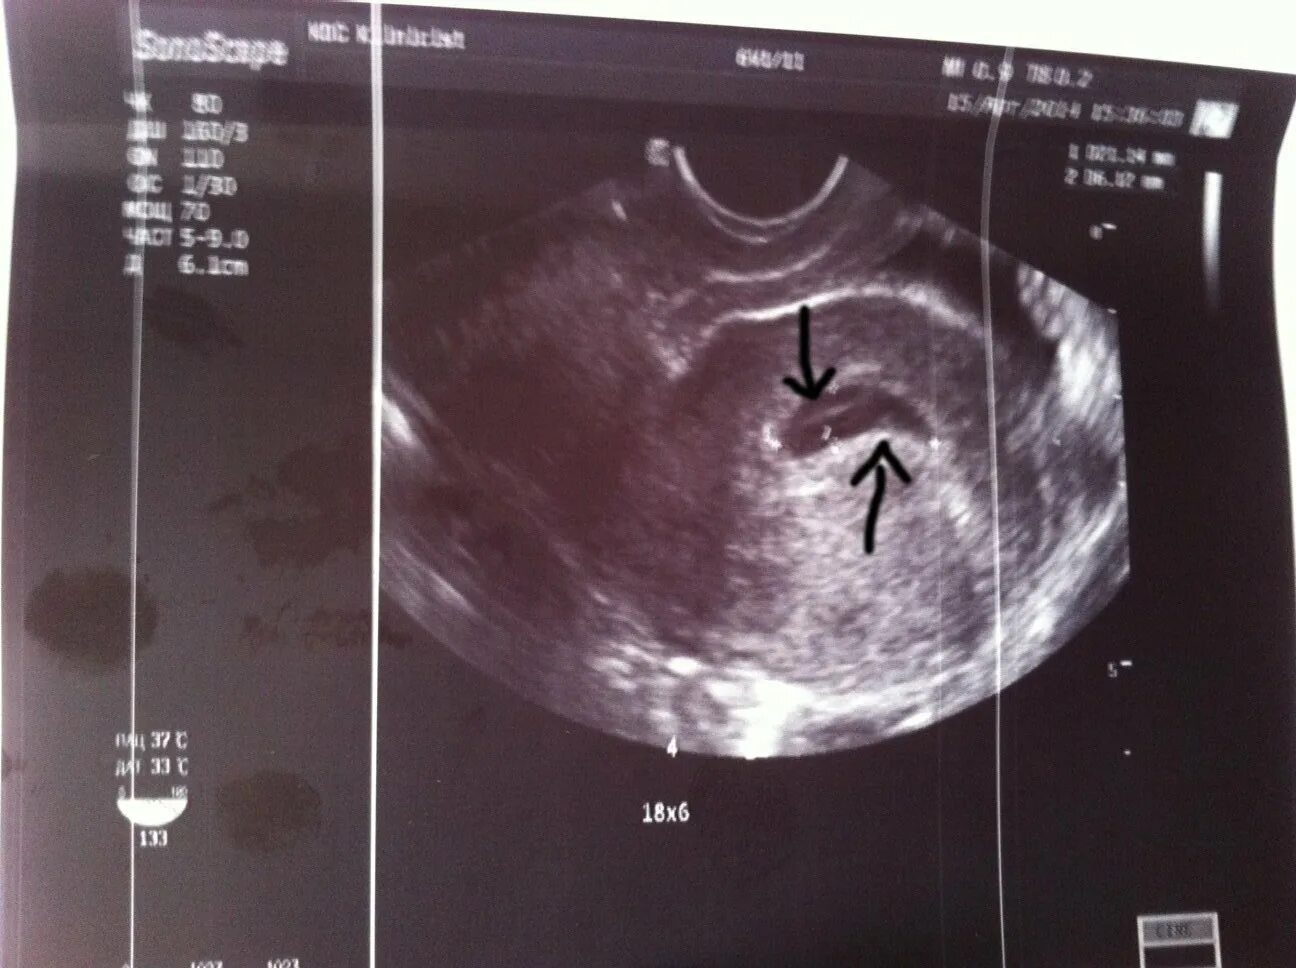

Эмбрион 4 недели 4 дня